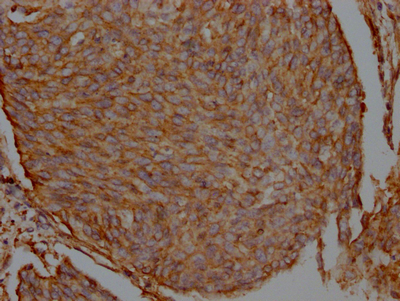

IHC image of CSB-RA548809A0HU diluted at 1:100 and staining in paraffin-embedded human cervical cancer performed on a Leica BondTM system. After dewaxing and hydration, antigen retrieval was mediated by high pressure in a citrate buffer (pH 6.0). Section was blocked with 10% normal goat serum 30min at RT. Then primary antibody (1% BSA) was incubated at 4℃ overnight. The primary is detected by a Goat anti-rabbit IgG polymer labeled by HRP and visualized using 0.05% DAB.

產(chǎn)品描述:CSB-RA548809A0HU重組單克隆抗體是針對(duì)FLNA蛋白研發(fā)的高特異性檢測(cè)工具。FLNA(Filamin A)作為重要的細(xì)胞骨架調(diào)控蛋白,通過(guò)交聯(lián)肌動(dòng)蛋白纖維參與細(xì)胞形態(tài)維持、粘附遷移及胞內(nèi)信號(hào)轉(zhuǎn)導(dǎo),其功能異常與腫瘤轉(zhuǎn)移、神經(jīng)發(fā)育障礙及心血管疾病密切相關(guān)。本抗體經(jīng)ELISA驗(yàn)證顯示優(yōu)異的抗原結(jié)合能力,免疫組化實(shí)驗(yàn)在1:50-200稀釋范圍內(nèi)可清晰呈現(xiàn)組織樣本中FLNA的亞細(xì)胞定位,切片顯色背景干凈且信號(hào)特異性強(qiáng)。采用重組表達(dá)技術(shù)制備保障了批次間穩(wěn)定性,適用于探究FLNA在細(xì)胞骨架重塑、腫瘤微環(huán)境調(diào)控、血管生成等領(lǐng)域的分子機(jī)制研究,特別推薦用于石蠟包埋組織切片的蛋白分布分析或體外實(shí)驗(yàn)?zāi)P偷牡鞍妆磉_(dá)檢測(cè),為細(xì)胞生物學(xué)、病理生理學(xué)等領(lǐng)域的基礎(chǔ)研究提供可靠工具。

Application Recommended Dilution IHC 1:50-1:200 -